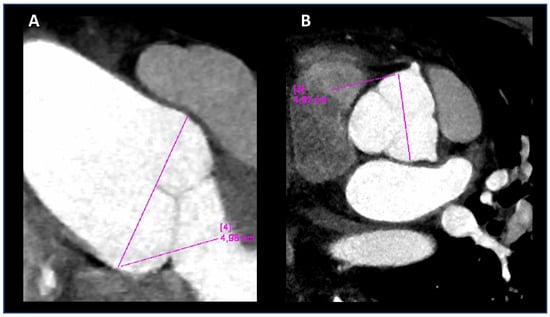

| Aortc root-z-score | 2.8 | 3.0 | 2.35 | N.R. | - | 5.0 before surgery |

| Ao | - | - | 31 normal size | Normal size | Normal size | Surgery at 38 years |

| Arterial aneurysm | - | - | - | - | - | Left common iliac, abdominal aorta, mild ectasia 14 × 16 (mm) |

| Arterial tortuosity | - | - | - | - | - | Arterial tortuosity iliacs |